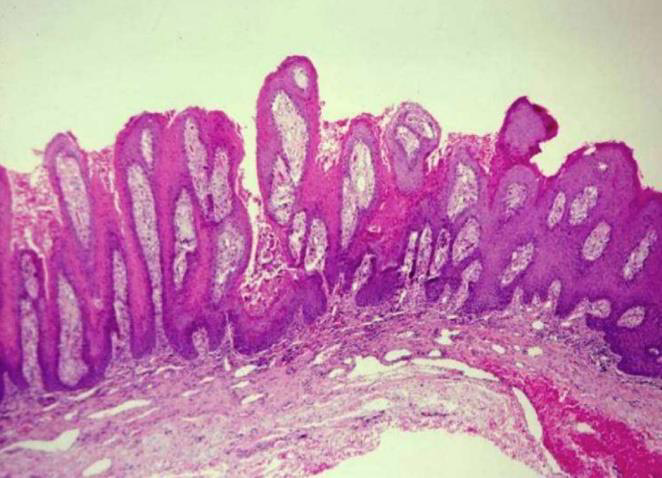

| Verruciform xanthoma (非 HPV) | Leasion 旁,異常免疫反應 | 口腔 > 皮膚 > 性器 | 油脂撐起 epi. 形成 Verruciform。非 Metabolic   |

|||

|

||||||

- xanthoma

- 吃了油脂的 Macrophage 細胞,CD63+, CD68+, CD163+ IHC8+,diastase-PAS染色+